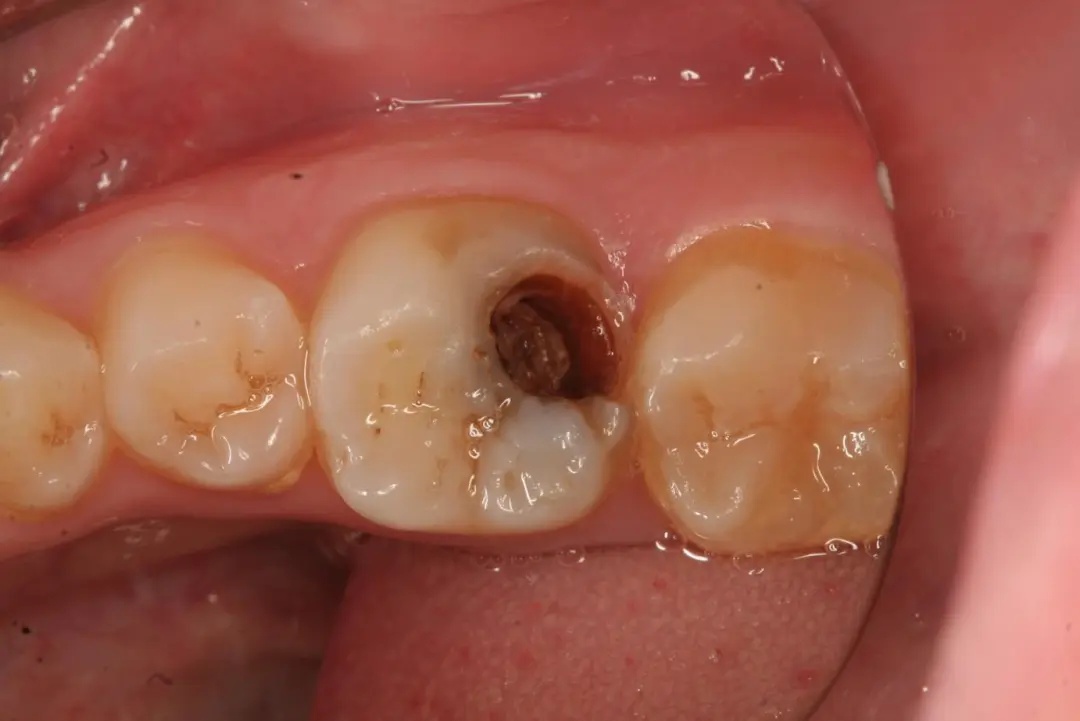

很多小伙伴有过这样的经历:牙疼得翻天覆地、彻夜难眠,心想“一定要找个时间去看牙!”但是一不疼了又想“看牙太可怕了,还是以后再说吧!”结果一拖再拖,反而变本加厉,无奈只能鼓起勇气去看了牙医,上来就想让医生补掉蛀牙,但是这种情况往往已经没办法直接补牙了…… 牙齿龋坏可以分为哪几种? 哪些情况可以直接补牙? 根据蛀牙的深浅,可以分为以下几种: 浅龋 牙齿咬合面有较深的黑线,常见于后牙,说明开始蛀牙了,牙釉质被破坏。这时候往往没有任何不适的症状,容易被忽视。 中龋和深龋 牙齿出现龋洞,冷热酸甜刺激时会敏感,或者食物残渣滞留在龋洞内时会引起酸痛,这种情况说明细菌已经侵入到牙本质中层或深层,如果没有明显的自发性疼痛,大部分情况还是可以进行直接充填的。 而又有哪些牙齿不能直接补牙呢? 有什么治疗的方法呢? 1.蛀牙在无任何刺激的情况下,出现夜间痛或自发痛情况,说明牙神经已经受到细菌感染,发生了牙髓炎,这种情况需要进行根管治疗。 2.蛀牙时间过长,牙神经已经感染坏死,引起牙根发炎。这种情况需要医生结合临床检查和X线片检查,判断牙齿龋坏的大小、根尖炎症的程度,以判断牙齿是否可以保留。若可以保留,即进行根管治疗;若无法保留,则需要拔除。 3.蛀牙面积过大且深,直接补牙极易脱落,效果较差。这种情况需要进行根管治疗后通过修复(全冠、嵌体等)的方法来解决。 小 结 所以,如果大家发现自己有蛀牙,应该尽早修补,以阻止牙齿进一步龋坏。若不及时进行治疗,龋洞就会越来越大,进而引起牙髓炎、根尖炎,甚至残根、残冠,直至需要拔牙。早发现、早治疗,效果就越好,花钱也越少。大家一定要定期检查牙齿哦!